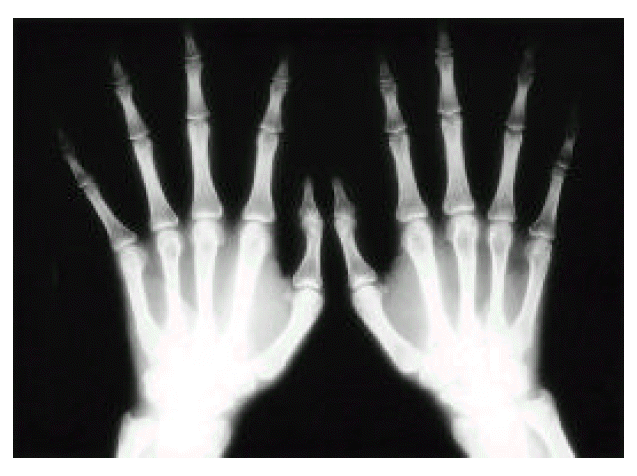

The blood pressure was 130/80 mmHg, the pulse was 112/min, the temperature was 37.4°C, and the respirations were 20/min. On examination, he appeared chronically ill. He was noted to have tall and thin stature with long tapered extremities and spider-like appearance of both hands. A grade III/VI holosystolic murmur was heard at the apex, with prominent radiation to the axilla. There were no palpable hepatosplenomegaly and lymph nodes. An ophthalmic examination by slit lamp showed lower lens zonular fibers due to mild upward displacement of lens in both eyes, that is, ecopia lentis, but he had adequate vision (Fig. 1).

Fig. 1.

Ophthalmic examination by slit lamp showing ectopia lentis in right eye.